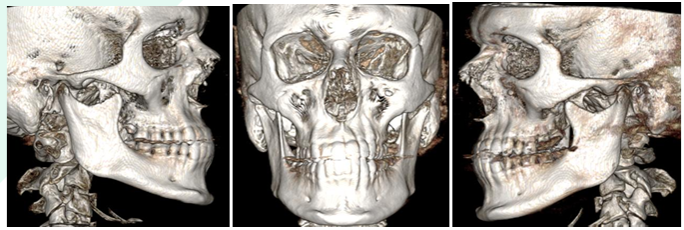

– Precise measurements and high-resolution annotated screenshots

TMJ evaluation

Head and neck reporting

Reporting of CBCT scans done your practice

Find some sample reports in PDF here: